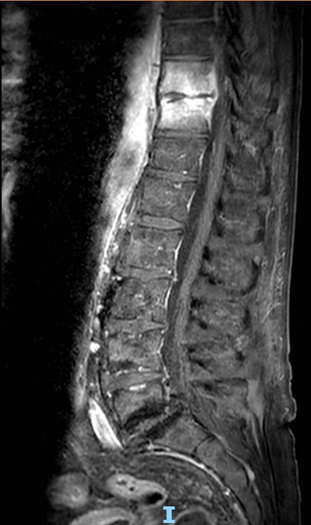

Figure 2: MRI of the thoracolumbar spine (T10-T11) showing vertebral signal abnormalities with T1 hypointensity, long-TR hyperintensity, and post-contrast enhancement involving the adjacent disc consistent with spondylodiscitis. A thin enhancing epidural collection (~3 mm thick, ~26 mm long) is seen in the anterior spinal canal, extending into the neural foramina. Bilateral paravertebral soft tissue enhancement, more evident on the left, shows a small fluid collection (~20 × 4 mm) suggestive of early abscess formation.

Ultimately, advanced imaging studies including MRI of the thoracolumbar spine (Figure 4), plain radiography of the right foot, and whole-body 18F-FDG PET/CT revealed two likely sources contributing to the persistent bacteremia: spondylodiscitis at the D10–D11 levels with associated epidural and paravertebral abscesses, and chronic osteomyelitic changes in the right foot. The spinal infection was characterized by vertebral involvement with adjacent epidural enhancement and paravertebral soft tissue abscesses, consistent with hematogenous seeding. The right foot, previously affected by Charcot neuroarthropathy and prior partial amputation, showed progression of osteolysis involving the remaining tarsal structures.